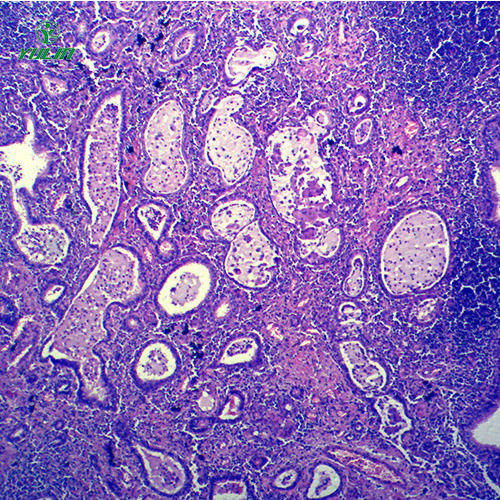

湖南炎症病理玻片

产品内容说明 /Product description

人体病理切片,炎症病理玻片,炎症病理玻片价格